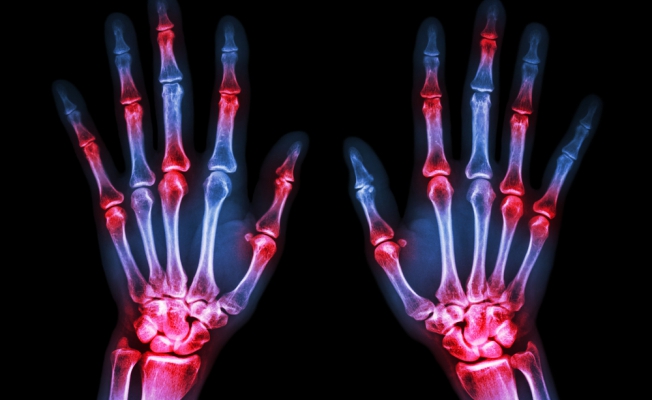

Малък по размер протеин, наречен GILZ, може да предотврати загубата на костна тъкан при артрит.

Вече учените разполагат с нови данни, потвърждаващи възможността за замяна на синтетичните глюкокортикоиди – основните средства за лечение на артрит – с многообещаващия протеин GILZ.

Тази възможност е налице, благодарение на това, че в основа на механизма на въздействие на глюкокортикоидите при артрит е и стимулирането на GILZ – прякото увеличаване на неговото равнище позволява да се избегнат страничните явления като загуба на костна тъкан.

В момента се разработва методика за създаване на лекарство за вътрешна употреба, което да даде на организма възможност за увеличаване на полезния протеин.